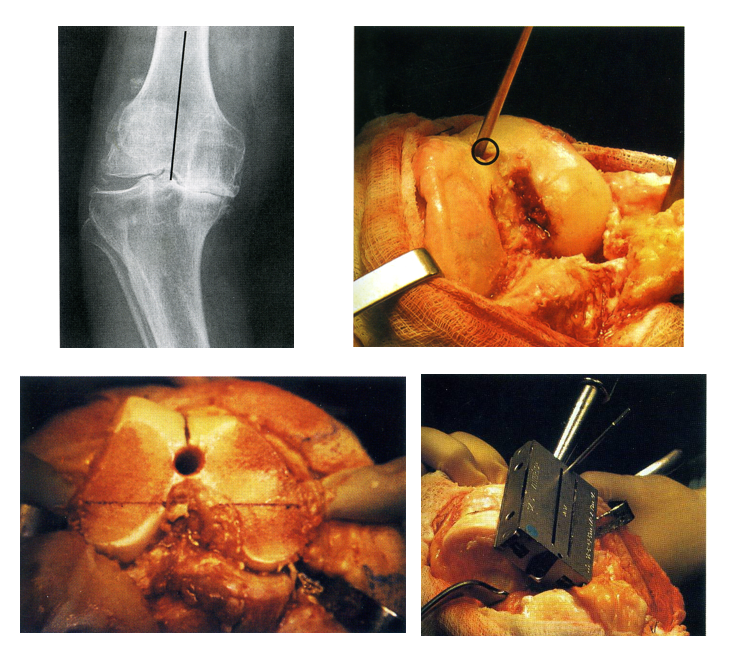

关键一、切骨与对线:正确判断定位系统

正确的下肢力线

正确的关节线和胫骨切骨量

切骨与伸屈间隙

后参照系统(最可靠)

恢复屈曲位的关节线